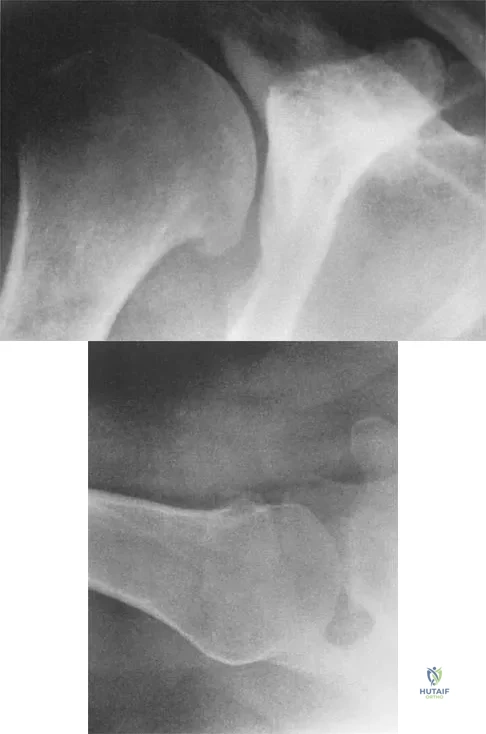

A 16-year-old girl has had pain in the left groin for the past 4 months. She notes that the pain is worse at night; however, she denies any history of trauma and has no constitutional symptoms. There is no history of steroid or alcohol use. Examination reveals pain in the left groin with rotation of the hip. There is no associated soft-tissue mass. A radiograph and MRI scan are shown in Figures 32a and 32b, and biopsy specimens are shown in Figures 32c and 32d. What is the most likely diagnosis?

Explanation